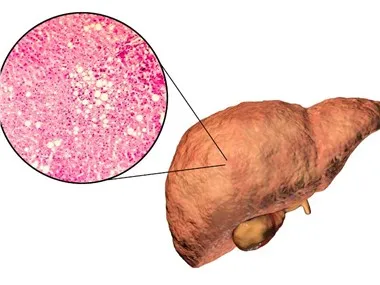

التخثر هو عملية منظمة للغاية تلعب دورًا مهمًا في منع فقدان الدم بعد الإصابة. ومع ذلك ، عندما يكون الجسم في حالة مؤيدة للتخثر ، يمكن أن يساهم في الإصابة بأمراض انسداد في كل من الشرايين والوريد. في Prisys Biotechnologies ، قمنا بتطوير العديد من النماذج والفحوصات في الجسم الحي التي تمكننا من تحديد التغيرات الديناميكية في حالة الإرقاء في الجسم. هذه النقاط النهائية حاسمة لعلم الأدوية وتقييمات السلامة في نماذج أمراض الأوعية الدموية.

تتضمن نماذج NHP الخاصة بنا نموذج النزيف في الجسم الحي ، ونموذج تحويلة Arterio-Venous (AV) ، ونموذج ركود Wessler ، ونموذج تخثر الشرايين الناجم عن FeCl3. مدة الدراسة القياسية لهذه النماذج هي ساعات ، مع تحديد نقاط نهاية الدراسة من خلال التصميم التجريبي المحدد. تشمل نقاط النهاية السريرية وقت النزيف / الوزن ، ووزن الجلطة / الجلطة ، واختبارات التخثر ، وسرعة تدفق الدم ، وتصوير التخثر.

تم تصميم نماذجنا لتوفير تقييمات شاملة للإرقاء ، وتقييمات السلامة ، ودراسات مضادة للتخثر ، ودراسات عوامل التخثر ، وتقييمات التخثر داخل الحجاج. تمكننا هذه النماذج من اكتساب فهم أعمق للآليات الأساسية للتخثر والتخثر ، وتوفر أداة قوية لتطوير واختبار علاجات جديدة لأمراض الأوعية الدموية.